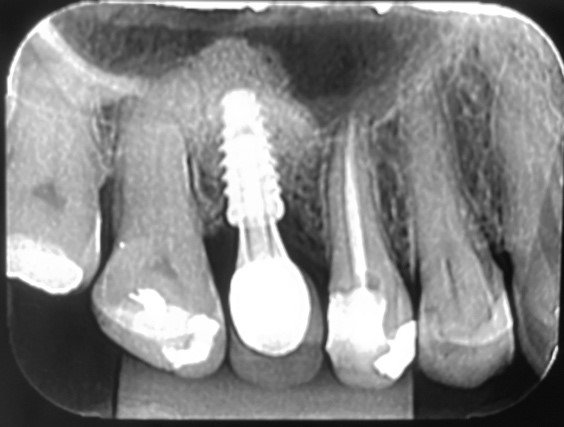

A irrigação da maxila é realizada por ramos de 2 principais vasos, a artéria alveolar superior posterior (AAPS) e a artéria infra-orbital (AIO), ramos da artéria maxilar 3,4. No estudo com tomografias de Khojastehpour et al 5 em 2016, eles encontraram anastomose na membrana entre as artérias AAPS e a AIO em 49.8% dos indivíduos, e do ponto de vista técnico nesssa condição, somente em casos de acidentes com rompimento da membrana sinusal poderia ocorrer hemorragias relevantes. Por outro lado, outros autores têm encontrado maior número de situações em que a AAPS se encontra intra-óssea, como nos estudos de Güncü et al 6 em 2011, e Ilgüi et al 7 em 2013, que observaram 68.2% e 71.1%, respectivamente. Quando a AAPS se encontra nessa última condição relatada, ocorre maior risco de dano vascular com hemorragia, especialmente se o canal vascular intra-ósseo for maior que 1 mm de espessura. Em média, alguns estudos têm demonstrado que a distância vertical do canal vascular da AAPS se apresenta próximo de 16 mm 5,7. Porém em casos de reabsorção do rebordo alveolar essa altura pode ser encontrada próximo de 11mm, segundo Rosano et al 4. A recomendação da tomografia como imagem de diagnóstico para identificação e mensuração da AAPS, pode estabelecer modificações estratégicas tanto na osteotomia, em relação ao desenho vertical e comprimento do implante, quanto na metodologia de instrumentação óssea. Podem ser usadas, por exemplo, ponteiras piezoelétricas sob irrigação para melhorar a visualização operatória e diminuir o risco de laceração vascular. As figuras de 1 a 12, demonstram caso clínico de técnica cirúrgica com osteotomia modificada, usando unidade piezo Mectron para remoção da parede lateral e preservar a AAPS, que foi diagnosticada em exame tomográfico durante a fase pré-operatória.